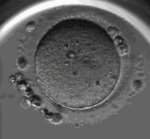

供卵试管婴儿可能会遗传妈妈的染色体异常基因供卵助孕,但一般概率比较小染色体问题供卵染色体问题供卵,因为医院卵子库里的卵子都是经过严格筛选的试管三代包成功,而且捐卵的年龄一般在26岁左右染色体问题供卵供卵宝宝,质量好通常比较好,成功率通常高达80%。 当然也不排除卵子异常的可能,需要根据实际情况判断。

一般来说,供卵所生孩子的基因来源是供卵者和男方。 从遗传的角度来说,母亲的染色体异常可以通过供卵试管传递给后代。 但是助孕机构,在供卵试管的情况下,会进行胚胎染色体筛查,可以对胚胎进行遗传性致病基因筛查,并选择健康的胚胎进行移植供卵试管遗传妈妈的染色体异常基因吗?,因此可以在很大程度上阻断母体致病基因的遗传。